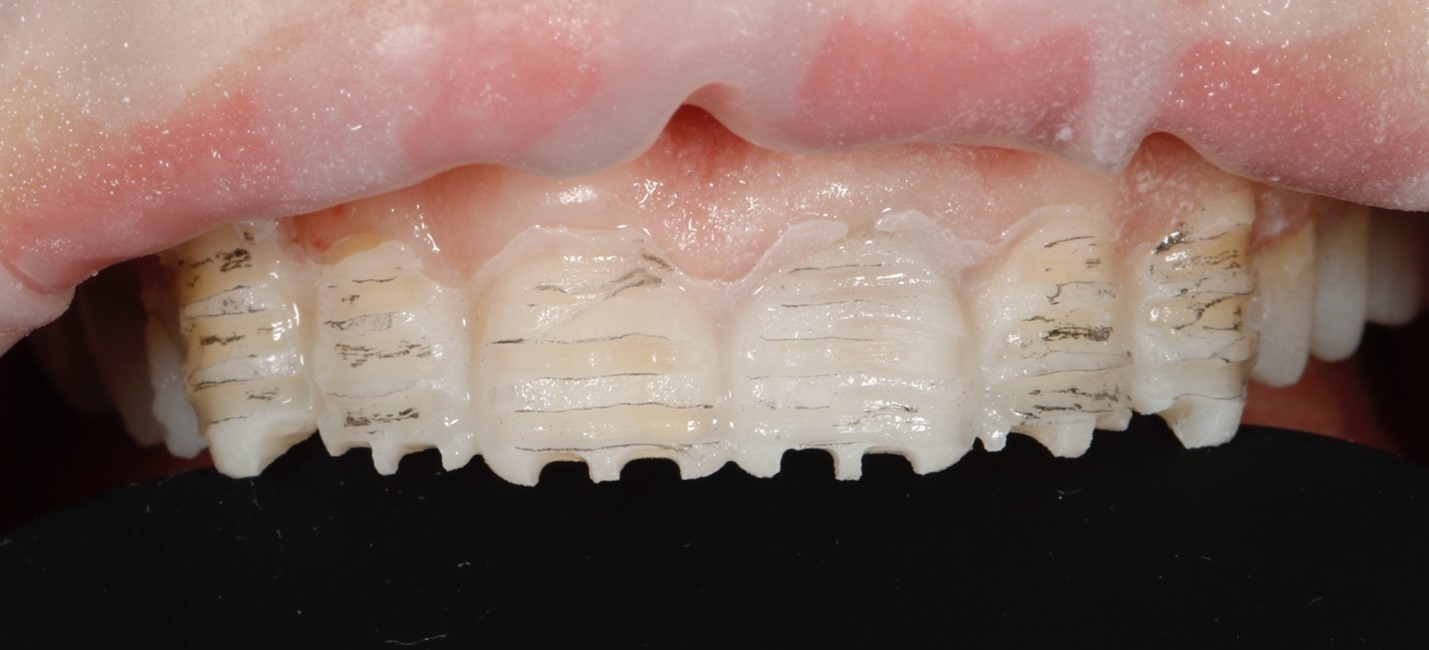

В третье посещение была проведена подготовка зубов под микроскопом под керамические реставрации. Изначала выполнена разметка зубов через временные реставрации, после чего был выполнен основной этап препарирования под контролем силиконовых ключей. Зуб 21 был подготовлен под коронку (Рисунок 3). Далее была проведена оценка цвета неподготовленный и подготовленных под керамические реставрации зубов (Рисунок 4). После снятия оттисков были изготовлены временные прямые реставрации Luxatemp A1 (DMG, Германия).

Рис. 3. Этапы препарирования зубов. А – разметка зубов через временные реставрации.

B – вид на этапе снятие оттисков.

С – проверка препарирования с помощью силиконового ключа.